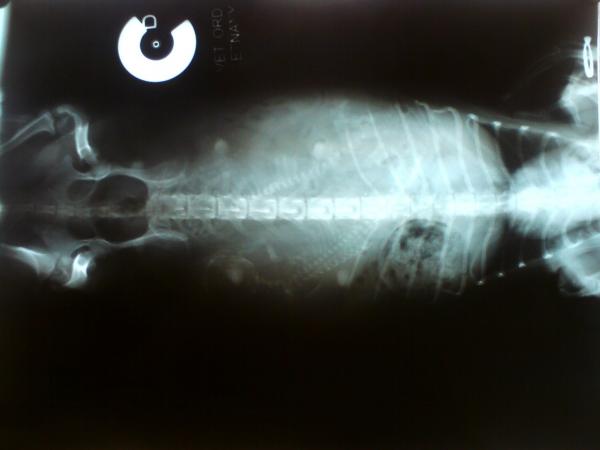

60. den březosti